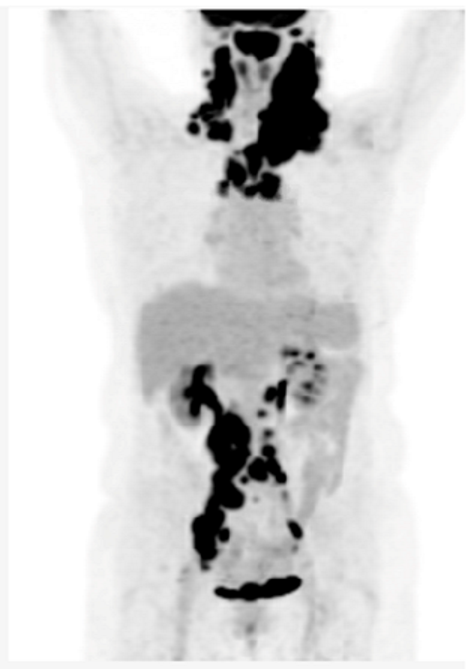

Key clinical features â˘â75-year-old female â˘âComorbidities include hypertension, type 2 diabetes and osteoarthritis â˘âPresented with fatigue, night sweats and bilateral neck fullness â˘âECOG PS 2 â˘âLabs: mild anemia 9.4 g/dL, LDH 420 U/L (ULN 240) â˘âPET/CT: lymphadenopathy above and below diaphragm, (maximum 14 cm) Diagnosis â˘âBiopsy of cervical lymph node suggests DLBCL, ABC subtype Initial Treatment â˘âTreated with 6 cycles of dose-reduced R-CHOP (with 1 delay due to infection) â˘âComplete response on post-treatment PET/CT â˘â20 months later, developed enlarged cervical nodes â˘âPET/CT and biopsy confirmed recurrent DLBCL Second-line Treatment â˘âNot considered to be a transplant/CAR-T cell candidate â˘âTreated with Polatuzumab-BR for 6 cycles, achieved a CR and remained in remission for 18 months Third-line Treatment â˘âShe now requires further therapy â˘âShe is now frailer with an ECOG PS 3, and is being considered for a BsAb |